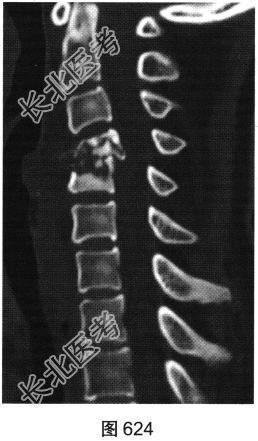

- [材料题] 患者男性,34岁,近数月乏力,偶有低热。颈部疼痛2个月余,逐渐加重,有轻压痛,颈部活动受限。

- 多项选择题2.[提示]患者行颈椎X线、CT和MRI检查,见图623~图628。首先应考虑患者为下列哪种疾病( )